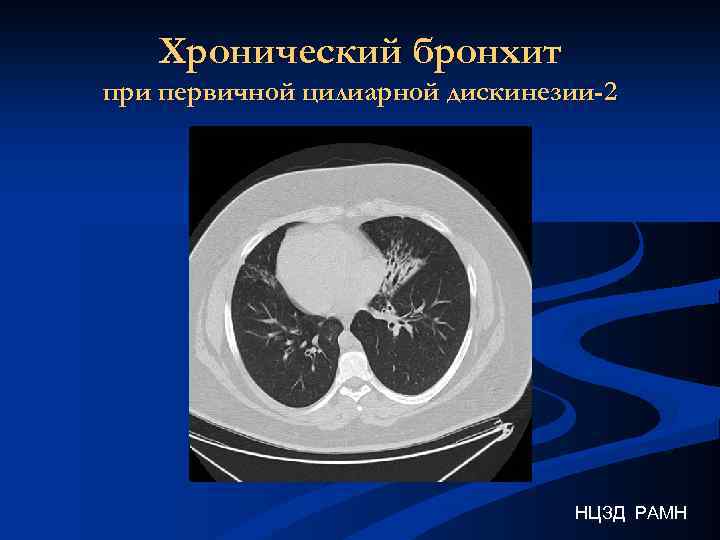

Хронический бронхит при первичной цилиарной дискинезии-2 НЦЗД РАМН